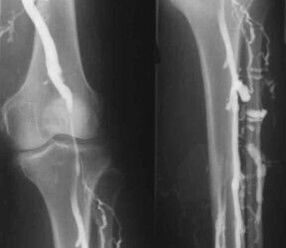

The most common instrumental diagnostic method is the use of ultrasound examination of the venous vessels of the legs.This technique allows you to visualize the vascular system and identify the degree of progression of the pathological process.

- Phlebography.